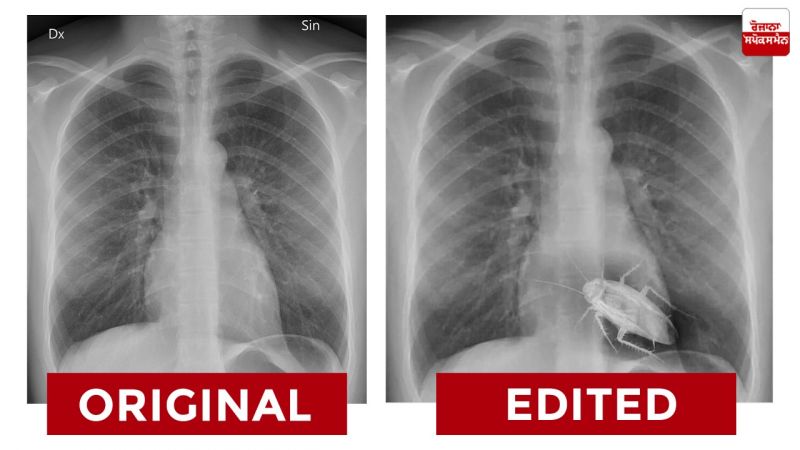

ਅਸਲ X-Ray ਅਤੇ ਵਾਇਰਲ X-Ray ਵਿਚਕਾਰ ਫਰਕ ਹੇਠਾਂ ਦਿੱਤੇ ਕੋਲਾਜ ਵਿਚ ਵੇਖਿਆ ਜਾ ਸਕਦਾ ਹੈ।

ਰੋਜ਼ਾਨਾ ਸਪੋਕਸਮੈਨ ਨੇ ਆਪਣੀ ਪੜਤਾਲ ਵਿਚ ਪਾਇਆ ਕਿ ਵਾਇਰਲ ਤਸਵੀਰ ਐਡੀਟੇਡ ਹੈ। ਇਸ X-Ray ਰਿਪੋਰਟ ਵਿਚ ਐਡੀਟਿੰਗ ਟੂਲਜ਼ ਦੀ ਮਦਦ ਨਾਲ ਕੋਕਰੋਚ ਨੂੰ ਚਿਪਕਾਇਆ ਗਿਆ ਹੈ।

ਨਤੀਜਾ- ਰੋਜ਼ਾਨਾ ਸਪੋਕਸਮੈਨ ਨੇ ਆਪਣੀ ਪੜਤਾਲ ਵਿਚ ਪਾਇਆ ਕਿ ਵਾਇਰਲ ਤਸਵੀਰ ਐਡੀਟੇਡ ਹੈ। ਇਸ X-Ray ਰਿਪੋਰਟ ਵਿਚ ਐਡੀਟਿੰਗ ਟੂਲਜ਼ ਦੀ ਮਦਦ ਨਾਲ ਕੋਕਰੋਚ ਨੂੰ ਚਿਪਕਾਇਆ ਗਿਆ ਹੈ।